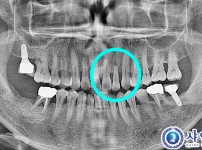

당일 발치 후 즉시 식립 8개 - 오스템 칼슘